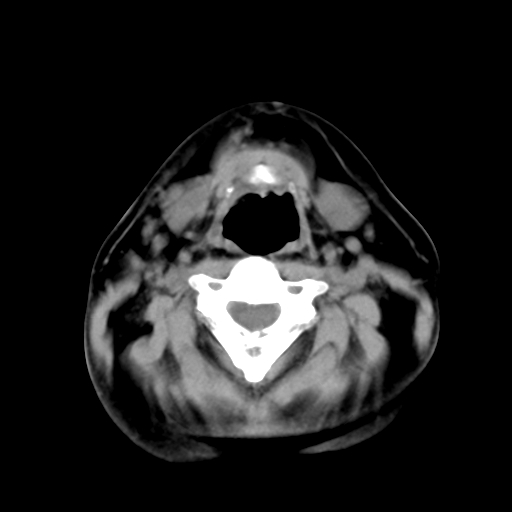

标题: CT24019:男,45岁,发现颈部肿物5个月。 [打印本页]

男,45岁,发现颈部肿物5个月,彩超示:双侧颈部及下颌部软组织增厚。

考虑双侧颈项部良性对称性脂肪增多症。